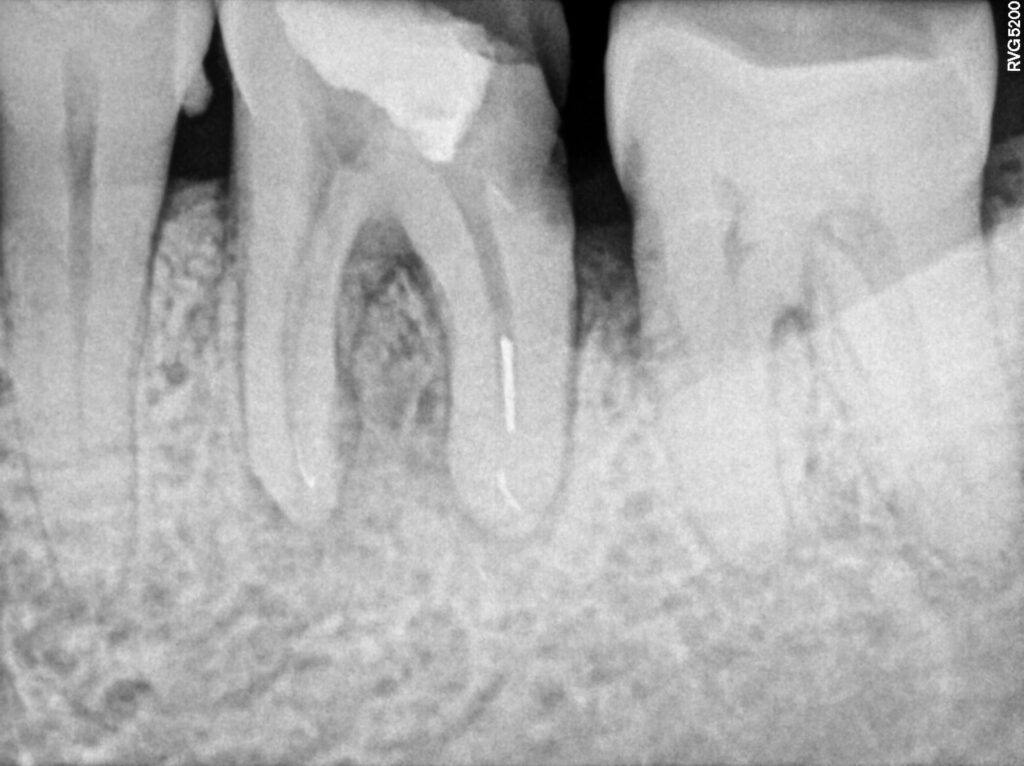

1. Separated instrument successfully removed under a microscope

Removing tiny instrument from canal is extremely difficult treatment and it requires high skills, precision and efforts.

The patient was referred to our practice to remove the instrument seperated accidentally by referral dentist and complete the treatment.

separated Instrumentis successfully removed under microscope

Root Canal with Dental Filling

Root canal completed along with restoration and patient referred back to dentist for further treatment